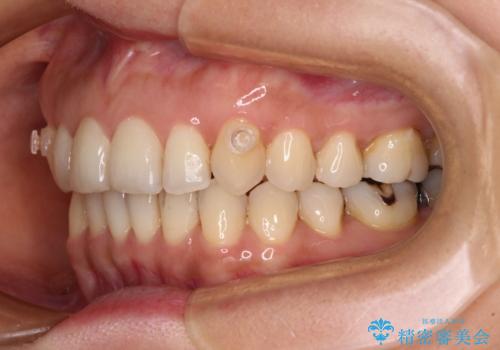

- 矯正治療の後戻りを気にして来院された患者様です。

後戻りは軽微であったので、インビザライン・ライトにより矯正治療を行うこととしました。